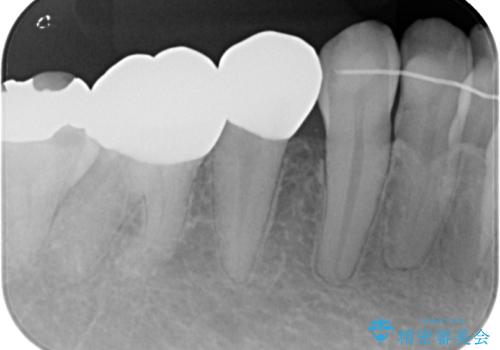

- 当院にて矯正治療を終えた患者様で銀歯を白くしたいとのことで来院された患者様です。神経の反応を確認し詰め物の範囲も大きいためフルジルコニアクラウンにて治療を行うことにしました。

拡大鏡視野下でメタルインレー、虫歯を除去しフルジルコニアクラウンに適した形に整えました。

歯と歯茎の間に圧排糸と言われる糸を入れてシリコーン印象材にて型どりをしました。